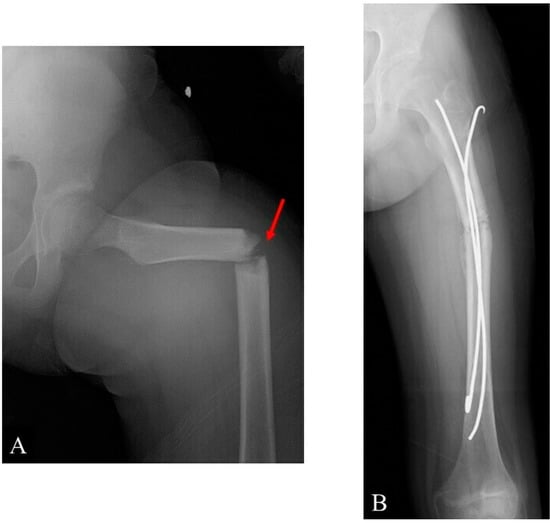

- Clinical and radiological evaluation of the osteoid osteoma.

- FEA to predict bone mechanical properties after the bone resection with the decided method, modified by tumor dimensions.

- Tumor resection and femoral stabilization, according to results of FEA.